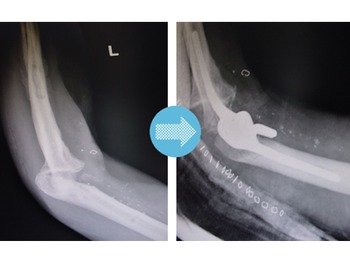

An elbow replacement surgery is especially indicated in a chronic inflamed and destroyed painful joint to give reasonable function and relief of pain.